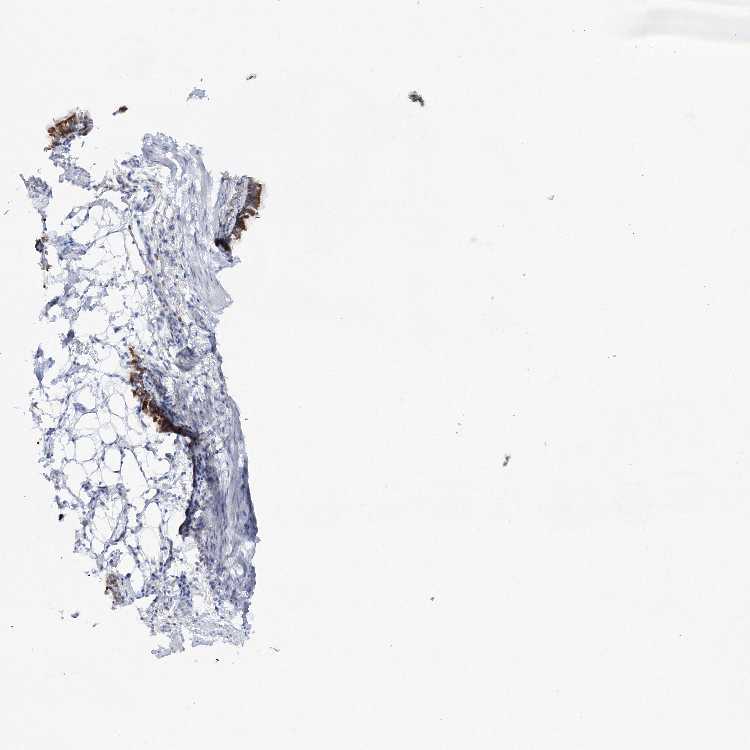

SOFT TISSUE 1 - Antibody stainingi

Antibody staining in the annotated cell types in the current human tissue is reported as not detected, low, medium, or high, based on conventional immunohistochemistry profiling in selected tissues. This score is based on the combination of the staining intensity and fraction of stained cells.

Each image is clickable and will lead to virtual microscopy that enables deeper exploration of all samples and also displays staining intensity scores, fraction scores and subcellular localization as well as patient and tissue information for each sample.

Antibody HPA038829

Fibroblasts Not detected

Peripheral nerve Not detected

SOFT TISSUE 2 - Antibody stainingi

Chondrocytes Not detected